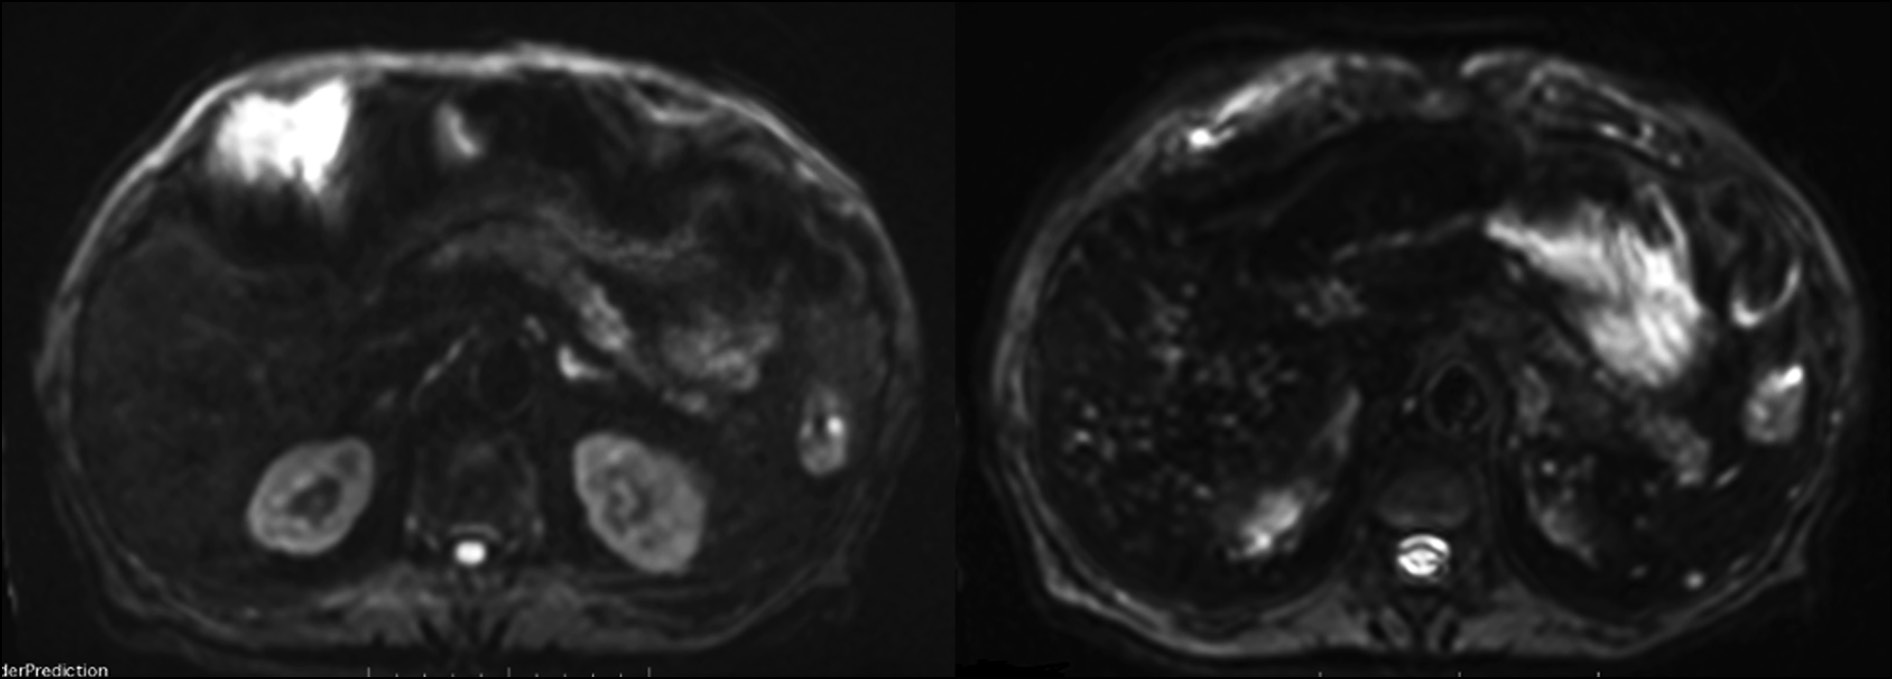

In diffusion-weighted imaging (DWI), the lesions persist as hyperintense at a low B-value (50 sec/mm2) but disappear at a high B-value (800) (Fig. 3).

Fig. 3. Axial MRI image with DWI sequence: hyperintense lesions at low B-value (50 sec/mm2) on the right, disappearing at high B-values on the left (800).